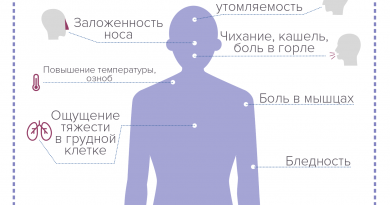

Устойчивый кашель является наиболее часто встречающимся симптомом рака легких на ранней стадии. Естественно, что кашель вообще часто сопровождает курильщиков, и его наличие не говорит о начале злокачественных новообразований.

Особенно, если вы заметили изменения в характере кашля. Кроме того, когда вдруг начали кашлять кровью или неожиданно большим количеством слизи, то в этом случае визит к врачу просто необходим. Обратите внимание также на изменения в тембре голоса. К примеру, когда у вас вдруг возникает хрипотца, или голос неожиданно меняется.

Тревожным симптомом являются изменения в дыхании, включая одышку. Они могут быть следствием проникновения опухоли в воздушные проходы, которые начинают закрываться. Иногда при дыхании возникает посвистывание, которое кажется чем-то невинным и даже забавным. Однако оно тоже говорит о проблемах с воздушными проходами. Никогда не игнорируйте боли в грудной клетке, особенно если они долго не проходят сами по себе. При опухолях легких эти боли также могут отдавать в грудь, плечи или спину.

Очень многие злокачественные новообразования сопровождаются необъяснимой потерей веса, которая происходит очень быстро. Рак легких часто выражается болями в костях, которые усиливаются в ночное время. Не следует игнорировать и головные боли, хотя в случае рака легких они могут свидетельствовать о том, что он уже дал метастазы в мозг, и победить болезнь невозможно.